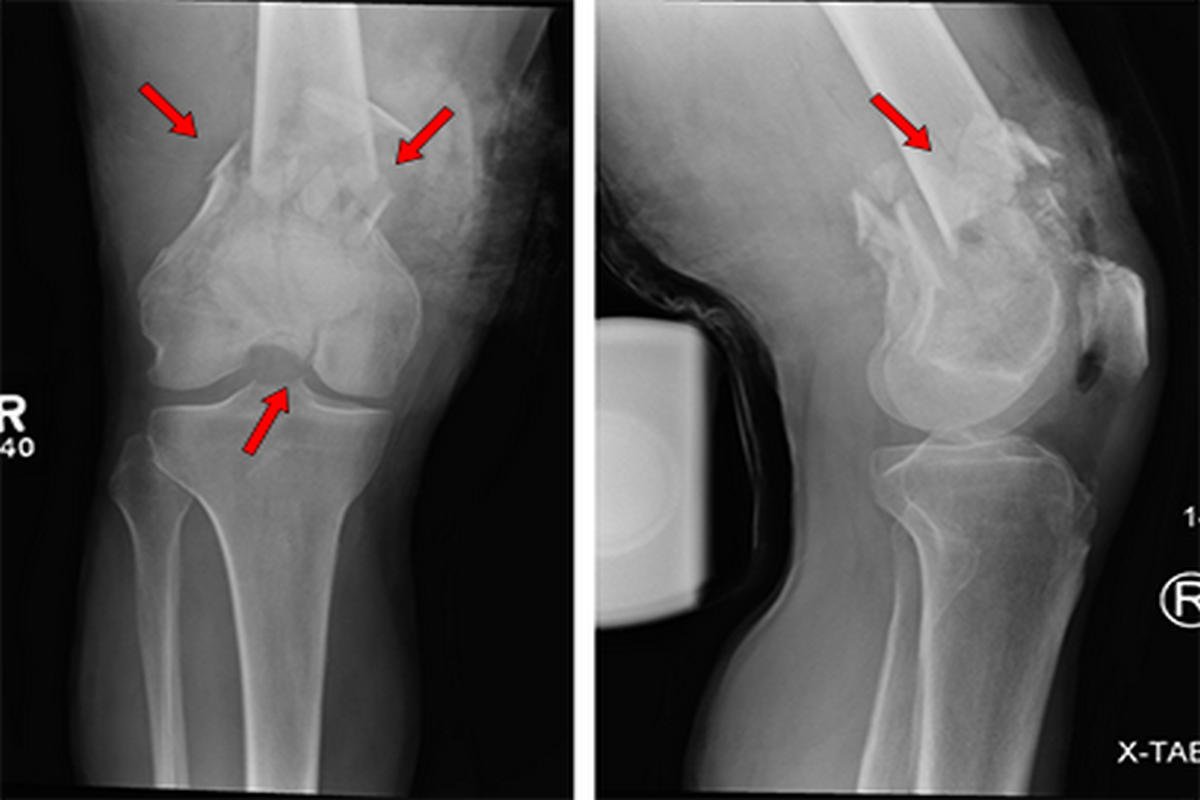

Διαϋπερκονδύλια κατάγματα μηριαίου

Τα διαϋπερκονδύλια κατάγματα εντοπίζονται στο κατώτερο άκρο του μηριαίου οστού, ακριβώς πάνω από την άρθρωση του γόνατος.

Συνήθως προκαλούνται από τραυματισμούς υψηλής ενέργειας, όπως τροχαία ατυχήματα ή πτώσεις από ύψος. Σε ηλικιωμένους ασθενείς με οστεοπόρωση, μπορεί να εμφανιστούν ακόμη και μετά από χαμηλής ενέργειας κάκωση.

Οι ασθενείς παρουσιάζουν έντονο πόνο, οίδημα, αδυναμία στήριξης του σκέλους και συχνά εμφανή παραμόρφωση. Η διάγνωση γίνεται με ακτινογραφίες, ενώ η αξονική τομογραφία είναι απαραίτητη για την ακριβή εκτίμηση της γραμμής και της πολυπλοκότητας του κατάγματος.

Η θεραπεία είναι κατά κανόνα χειρουργική και περιλαμβάνει οστεοσύνθεση με πλάκες και βίδες ή ενδομυελικούς ήλους, με στόχο την ανατομική ανάταξη και τη σταθερότητα. Συντηρητική αγωγή εφαρμόζεται σπάνια και μόνο σε ασθενείς που δεν μπορούν να υποβληθούν σε χειρουργείο.